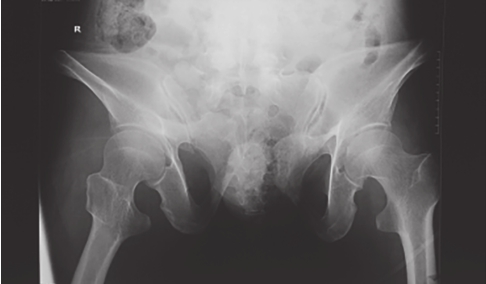

可显示骶骨、髂骨后上部、骶髂关节上方、耻骨联合、耻骨支上缘及髋臼顶弓等。可用于鉴别骨盆环骨折的前后移位、旋转畸形、耻骨联合分离等(图2-2、图2-3)。

图2-2 骨盆入口位X线片1

可见左侧髂骨体骨质破裂,部分骨块分离,累及髂骨翼及骶髂关节面;左侧耻骨上、下支骨折,累及耻骨联合,提示骨盆前环损伤;双侧骶髂关节对位可,并未发生前后旋转移位。

图2-3 骨盆入口位X线片2

可见右侧骶骨翼骨折,耻骨联合分离,提示骨盆前后环损伤,右半侧骨盆向后移位。